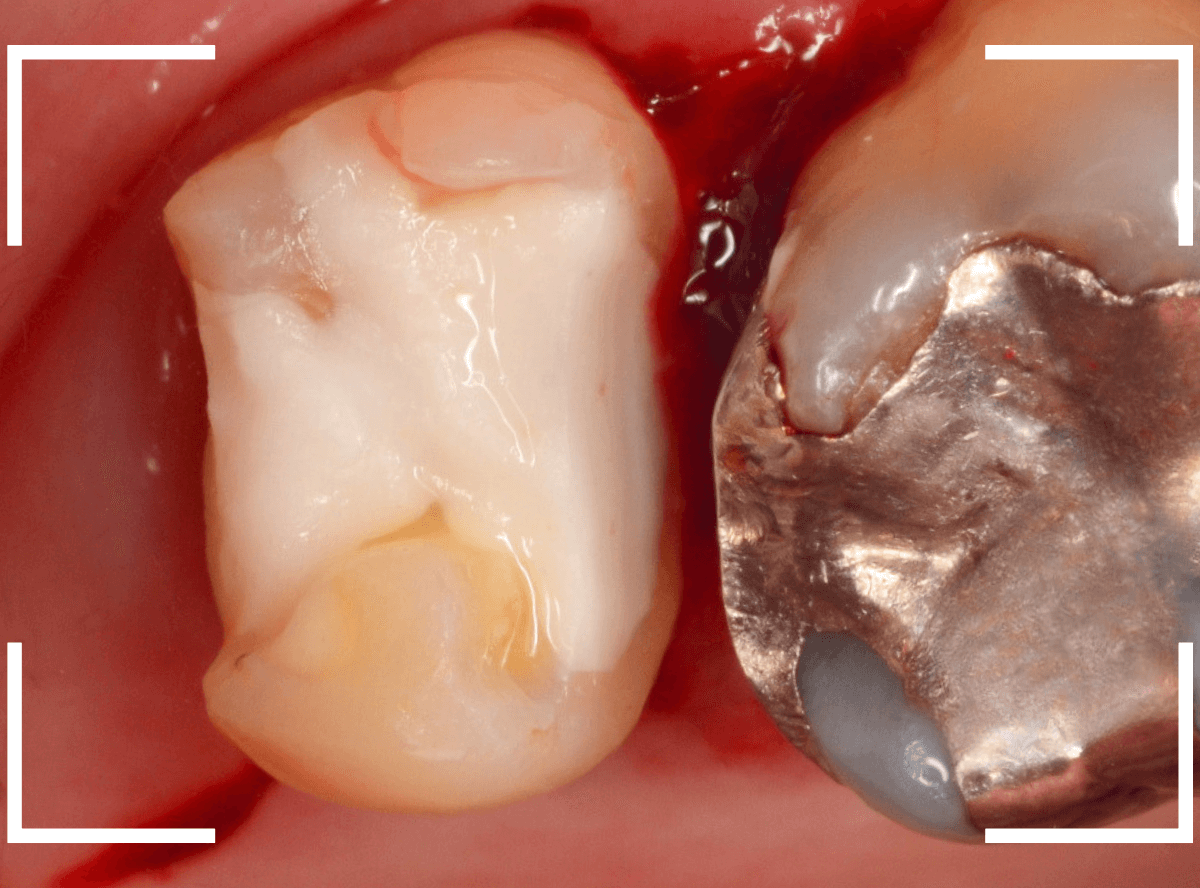

Case.15 歯の側面のレジンの中のわかりづらい虫歯

検診で、金属のつめ物のの中と、歯の側面に虫歯が見つかった方です。

まずは、手前(左)側の治療です。

こちらが、お口の中を見たところです。

〇部の中に虫歯があると思われます。

今回のように、金属のつめ物やレジン治療をしてある歯の側面の虫歯の診断はわかりづらく、難しいです。

金属のつめ物を外したところです。

この白いセメントの中に虫歯があると思われます。

セメントを除去したところです。

赤く染まっている部分が虫歯です。

真っ赤ですね(^^;)

まだ薄く染まっています。

もう少し除去する必要があります。

全ての虫歯が取れました、かなり深い神経まで近い虫歯でした。

金属のつめものをを外します。

つめものの下で虫歯になっていたせいで、虫歯と一緒に手前側のエナメル質がガリっと欠けてきました(><)

前の治療でつめたセメントを外しつつ、虫歯治療を行います。

写真ではわかりづらいですが、赤く染まった部分を中心に、虫歯がかなり広がっています。

虫歯を全て取り切ったところです。

神経スレスレの部分まで広がった虫歯で、最後は神経に触らないようにエキスカを使った、手探りでの虫歯治療になりました。